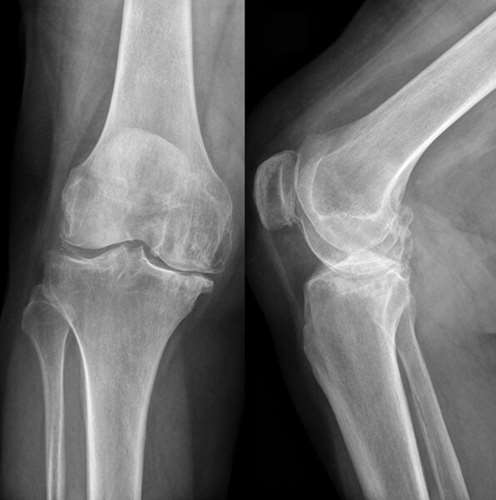

РОЗПІЗНАЙТЕ СКЛАДНИЙ СУГЛОБ, ЯКИЙ СКЛАДАЄТЬСЯ З ТРЬОХ КІСТОК, ОДНА З ЯКИХ РОЗТАШОВАНА В СУХОЖИЛКУ ЧОТИРИГОЛОВОГО М'ЯЗА СТЕГНА.

варіанти відповідей

СУГЛОБ СКЛАДНИЙ. УТВОРЕНИЙ СУГЛОБОВИМИ ПОВЕРХНЯМИ МЕДІАЛЬНОГО І ЛАТЕРАЛЬНОГО ВИРОСТКІВ, ЯКІ Є В ОБОХ КІСТКАХ, ЩО ЙОГО УТВОРЮЮТЬ. РОЗПІЗНАЙТЕ СУГЛОБ.

КОЛІННИЙ С.

ЛІКТЬОВИЙ С.

ГОМІЛКОВО--СТОПНИЙ С.

ПРОМЕНЕВО-ЗАП'ЯСТКОВИЙ С.